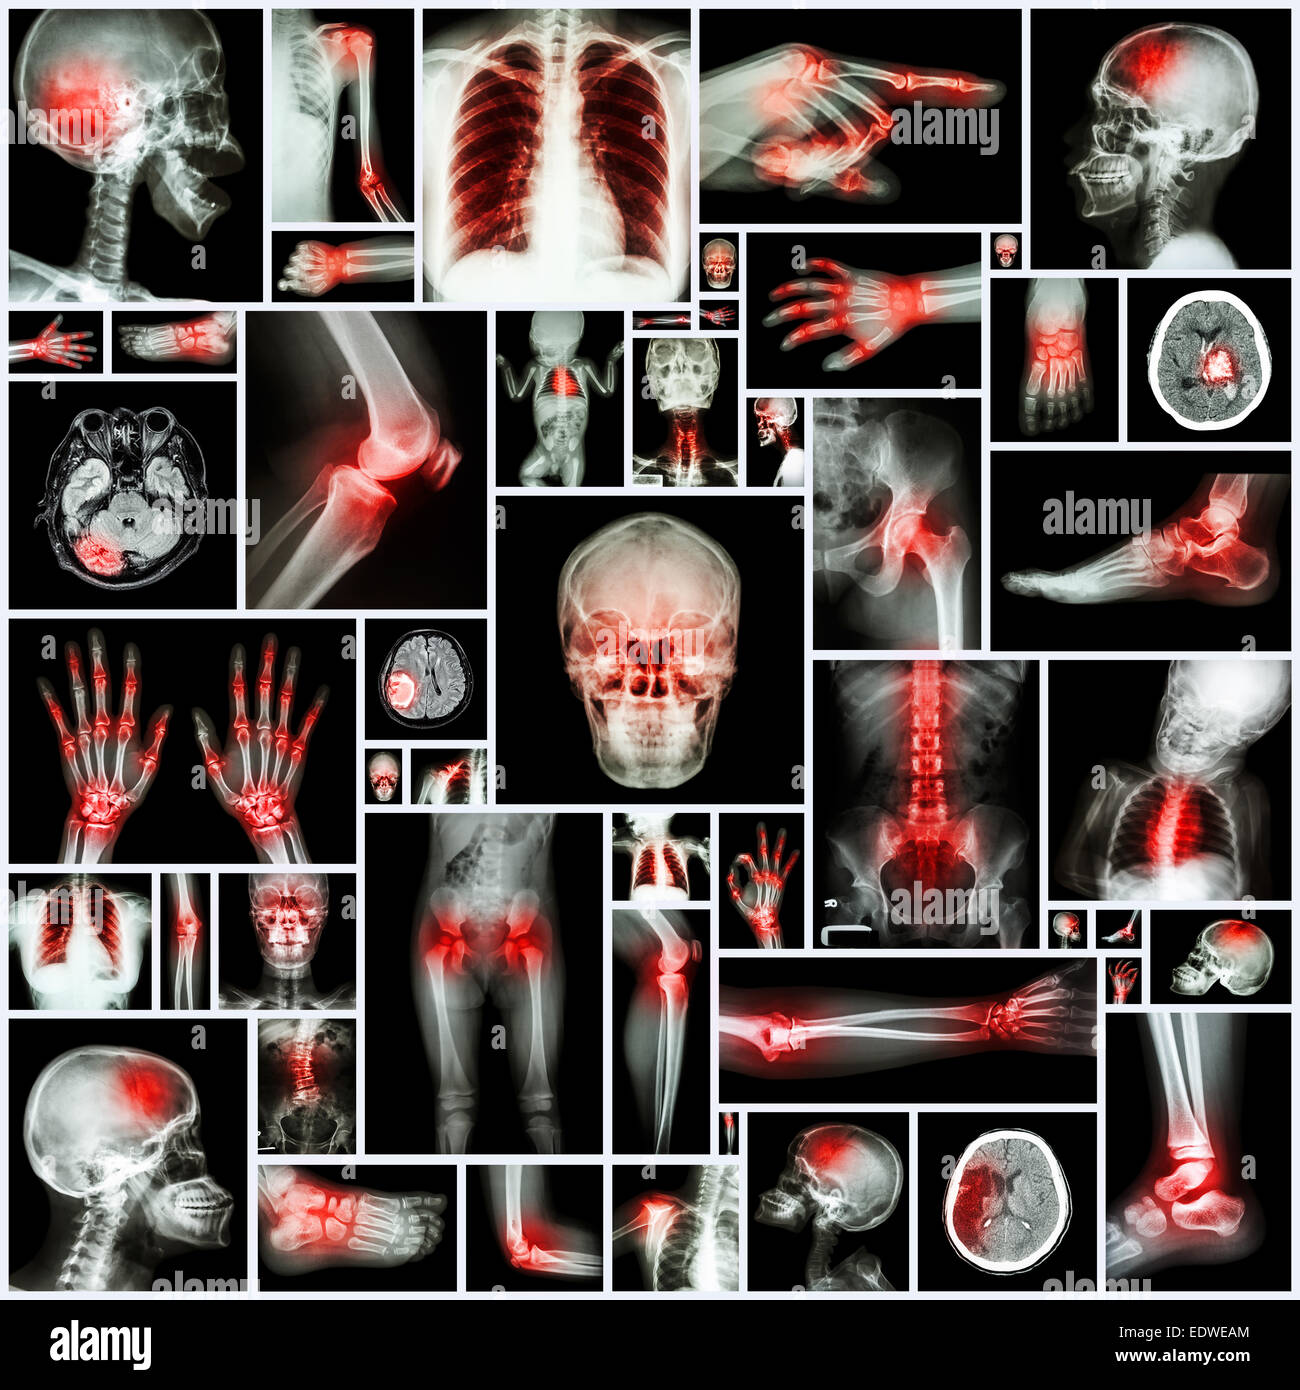

Collection X-ray et d'organes multiples à l'arthrite rhumatoïde (commune de multiples,la goutte) Banque D'Imageshttps://www.alamyimages.fr/image-license-details/?v=1https://www.alamyimages.fr/photo-image-collection-x-ray-et-d-organes-multiples-a-l-arthrite-rhumatoide-commune-de-multiples-la-goutte-77392076.html

Collection X-ray et d'organes multiples à l'arthrite rhumatoïde (commune de multiples,la goutte) Banque D'Imageshttps://www.alamyimages.fr/image-license-details/?v=1https://www.alamyimages.fr/photo-image-collection-x-ray-et-d-organes-multiples-a-l-arthrite-rhumatoide-commune-de-multiples-la-goutte-77392076.htmlRFEDWEAM–Collection X-ray et d'organes multiples à l'arthrite rhumatoïde (commune de multiples,la goutte)

Collection X-ray et d'organes multiples à l'arthrite rhumatoïde (commune de multiples,la goutte) Banque D'Imageshttps://www.alamyimages.fr/image-license-details/?v=1https://www.alamyimages.fr/photo-image-collection-x-ray-et-d-organes-multiples-a-l-arthrite-rhumatoide-commune-de-multiples-la-goutte-77392073.html

Collection X-ray et d'organes multiples à l'arthrite rhumatoïde (commune de multiples,la goutte) Banque D'Imageshttps://www.alamyimages.fr/image-license-details/?v=1https://www.alamyimages.fr/photo-image-collection-x-ray-et-d-organes-multiples-a-l-arthrite-rhumatoide-commune-de-multiples-la-goutte-77392073.htmlRFEDWEAH–Collection X-ray et d'organes multiples à l'arthrite rhumatoïde (commune de multiples,la goutte)

Collection X-ray partie multiples des droits de l'arthrite et la goutte (maladie,plusieurs , la polyarthrite rhumatoïde, la maladie de coeur congénitale,course) Banque D'Imageshttps://www.alamyimages.fr/image-license-details/?v=1https://www.alamyimages.fr/photo-image-collection-x-ray-partie-multiples-des-droits-de-l-arthrite-et-la-goutte-maladie-plusieurs-la-polyarthrite-rhumatoide-la-maladie-de-coeur-congenitale-course-77404848.html

Collection X-ray partie multiples des droits de l'arthrite et la goutte (maladie,plusieurs , la polyarthrite rhumatoïde, la maladie de coeur congénitale,course) Banque D'Imageshttps://www.alamyimages.fr/image-license-details/?v=1https://www.alamyimages.fr/photo-image-collection-x-ray-partie-multiples-des-droits-de-l-arthrite-et-la-goutte-maladie-plusieurs-la-polyarthrite-rhumatoide-la-maladie-de-coeur-congenitale-course-77404848.htmlRFEDX2JT–Collection X-ray partie multiples des droits de l'arthrite et la goutte (maladie,plusieurs , la polyarthrite rhumatoïde, la maladie de coeur congénitale,course)

Collection X-ray des multiples d'organes et la chirurgie orthopédique et de multiples maladies (tuberculose pulmonaire , la goutte, l'arth Banque D'Imageshttps://www.alamyimages.fr/image-license-details/?v=1https://www.alamyimages.fr/photo-image-collection-x-ray-des-multiples-d-organes-et-la-chirurgie-orthopedique-et-de-multiples-maladies-tuberculose-pulmonaire-la-goutte-l-arth-77008650.html

Collection X-ray des multiples d'organes et la chirurgie orthopédique et de multiples maladies (tuberculose pulmonaire , la goutte, l'arth Banque D'Imageshttps://www.alamyimages.fr/image-license-details/?v=1https://www.alamyimages.fr/photo-image-collection-x-ray-des-multiples-d-organes-et-la-chirurgie-orthopedique-et-de-multiples-maladies-tuberculose-pulmonaire-la-goutte-l-arth-77008650.htmlRFED818X–Collection X-ray des multiples d'organes et la chirurgie orthopédique et de multiples maladies (tuberculose pulmonaire , la goutte, l'arth

Collection X-ray des multiples d'organes et la chirurgie orthopédique et de multiples maladies (tuberculose pulmonaire , la goutte, l'arth Banque D'Imageshttps://www.alamyimages.fr/image-license-details/?v=1https://www.alamyimages.fr/photo-image-collection-x-ray-des-multiples-d-organes-et-la-chirurgie-orthopedique-et-de-multiples-maladies-tuberculose-pulmonaire-la-goutte-l-arth-77008652.html

Collection X-ray des multiples d'organes et la chirurgie orthopédique et de multiples maladies (tuberculose pulmonaire , la goutte, l'arth Banque D'Imageshttps://www.alamyimages.fr/image-license-details/?v=1https://www.alamyimages.fr/photo-image-collection-x-ray-des-multiples-d-organes-et-la-chirurgie-orthopedique-et-de-multiples-maladies-tuberculose-pulmonaire-la-goutte-l-arth-77008652.htmlRFED8190–Collection X-ray des multiples d'organes et la chirurgie orthopédique et de multiples maladies (tuberculose pulmonaire , la goutte, l'arth

X-ray plusieurs partie de la avec de multiples maladies (accident vasculaire cérébral, l'arthrite, la goutte, le rhumatisme, tumeur au cerveau, l'arthrose, etc.) Banque D'Imageshttps://www.alamyimages.fr/image-license-details/?v=1https://www.alamyimages.fr/photo-image-x-ray-plusieurs-partie-de-la-avec-de-multiples-maladies-accident-vasculaire-cerebral-l-arthrite-la-goutte-le-rhumatisme-tumeur-au-cerveau-l-arthrose-etc-77391487.html

X-ray plusieurs partie de la avec de multiples maladies (accident vasculaire cérébral, l'arthrite, la goutte, le rhumatisme, tumeur au cerveau, l'arthrose, etc.) Banque D'Imageshttps://www.alamyimages.fr/image-license-details/?v=1https://www.alamyimages.fr/photo-image-x-ray-plusieurs-partie-de-la-avec-de-multiples-maladies-accident-vasculaire-cerebral-l-arthrite-la-goutte-le-rhumatisme-tumeur-au-cerveau-l-arthrose-etc-77391487.htmlRFEDWDHK–X-ray plusieurs partie de la avec de multiples maladies (accident vasculaire cérébral, l'arthrite, la goutte, le rhumatisme, tumeur au cerveau, l'arthrose, etc.)

X-ray plusieurs partie de la avec de multiples maladies (accident vasculaire cérébral, l'arthrite, la goutte, le rhumatisme, tumeur au cerveau, l'arthrose, etc.) Banque D'Imageshttps://www.alamyimages.fr/image-license-details/?v=1https://www.alamyimages.fr/photo-image-x-ray-plusieurs-partie-de-la-avec-de-multiples-maladies-accident-vasculaire-cerebral-l-arthrite-la-goutte-le-rhumatisme-tumeur-au-cerveau-l-arthrose-etc-77391482.html

X-ray plusieurs partie de la avec de multiples maladies (accident vasculaire cérébral, l'arthrite, la goutte, le rhumatisme, tumeur au cerveau, l'arthrose, etc.) Banque D'Imageshttps://www.alamyimages.fr/image-license-details/?v=1https://www.alamyimages.fr/photo-image-x-ray-plusieurs-partie-de-la-avec-de-multiples-maladies-accident-vasculaire-cerebral-l-arthrite-la-goutte-le-rhumatisme-tumeur-au-cerveau-l-arthrose-etc-77391482.htmlRFEDWDHE–X-ray plusieurs partie de la avec de multiples maladies (accident vasculaire cérébral, l'arthrite, la goutte, le rhumatisme, tumeur au cerveau, l'arthrose, etc.)